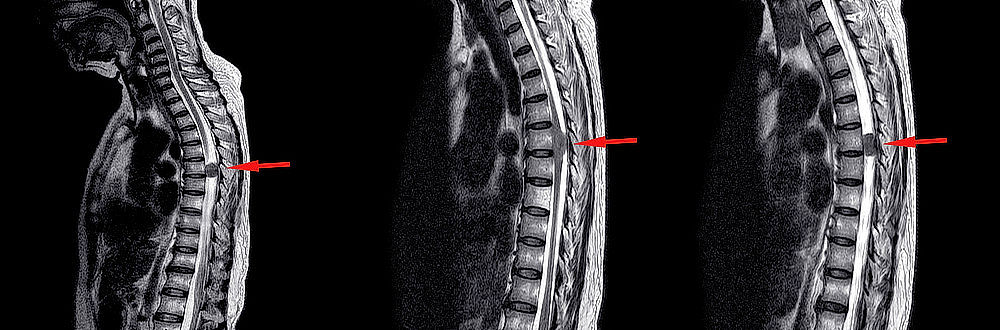

Odborníci rozlišují různé typy nádorů míchy, například podle místa jejich vzniku [1] (viz také obr. 1):

Obrázek 1: Klasifikace nádorů míchy podle místa jejich vzniku – schematický nákres. (Zdroj: By Mustapha Mansour, https://www.flickr.com/photos/134614741@N02/22133876283, CC BY-NC-SA 2.0)

V závislosti na výsledcích dosavadních vyšetření může lékař pacienta odeslat na vyšetření magnetickou rezonancí (MRI) nebo výpočetní tomografií (CT). Lékaři podílející se na diagnostice tak získají přehled o stavu míchy a jejího okolí. Zobrazovací vyšetření pomůže mimo jiné vyloučit jiná onemocnění s podobnými příznaky, například výhřez meziobratlové ploténky nebo poranění páteře.

Pokud je odhalen nádor, lékaři na základě snímků z magnetické rezonance mohou učinit první závěry o jeho typu a umístění. V závislosti na konkrétním případu jsou pak prováděna další vyšetření. Teprve v okamžiku, kdy jsou k dispozici výsledky všech potřebných vyšetření, lze naplánovat další léčebné kroky.